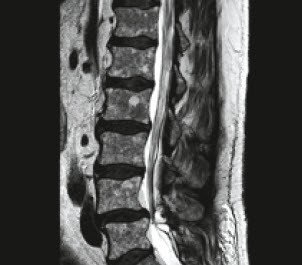

Aufgrund dieser Diagnose leiten wir eine chemotherapeutische Behandlung ein, was zu einer vollständigen Remission der Krankheit führt. In der Folge jedoch persistieren die belastungsabhängigen Rücken- / Bein-Beschwerden. Ein erneutes MRI (oben rechts) der Lendenwirbelsäule zeigt eine deutliche Einengung des Spinalkanals aufgrund von Abnützungserscheinungen bei einer sich neu gebildeten Zyste und epiduralem Fett. Drei Monate später wird der Patient in unserer Klinik mit einer Entlastungs- und Versteifungsoperation auf dem Niveau L4 / 5 operativ behandelt.